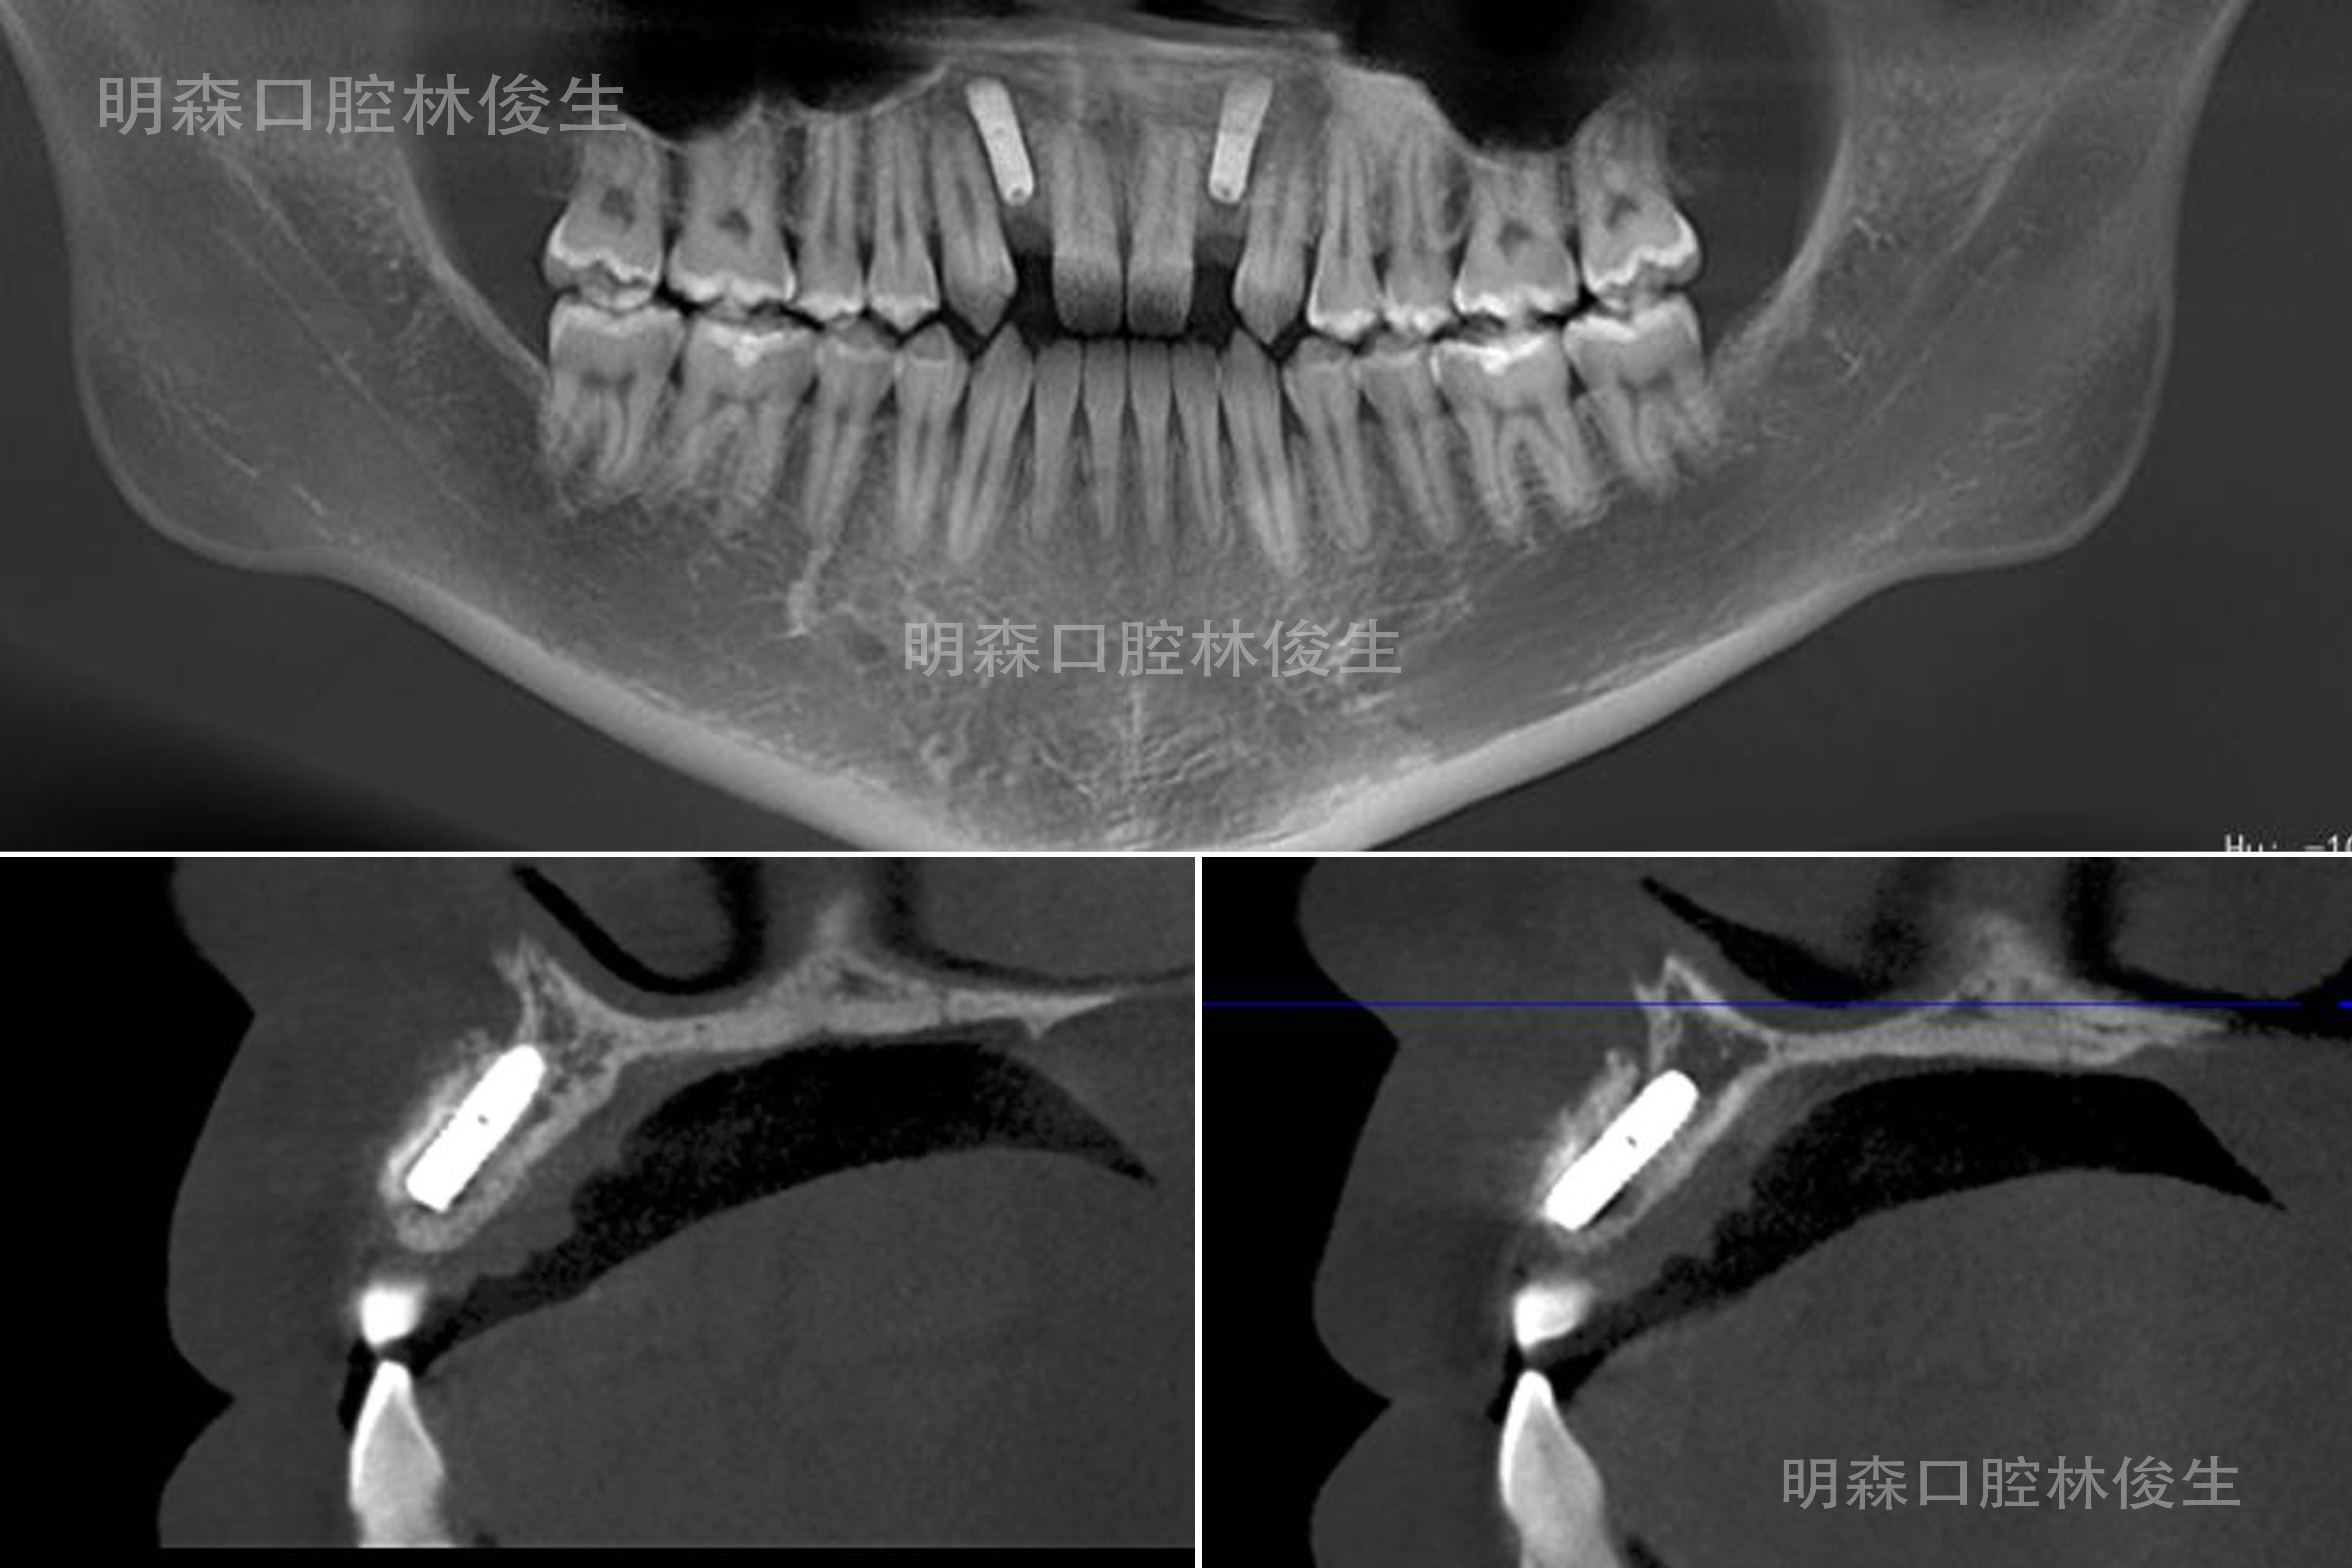

植骨术前术后对比(左前右后)

植骨术前术后对比(左前右后)

种植修复手术前

种植修复手术后

那位前牙先天性缺失2颗的21岁患者,修复难点主要是牙槽骨严重萎缩以及植体的植入点位!我们经过多学科联合就诊,采用种植修复治疗方式恢复先天性牙缺失患者的口颌功能,将手术分为骨增量与种植修复两期完成。